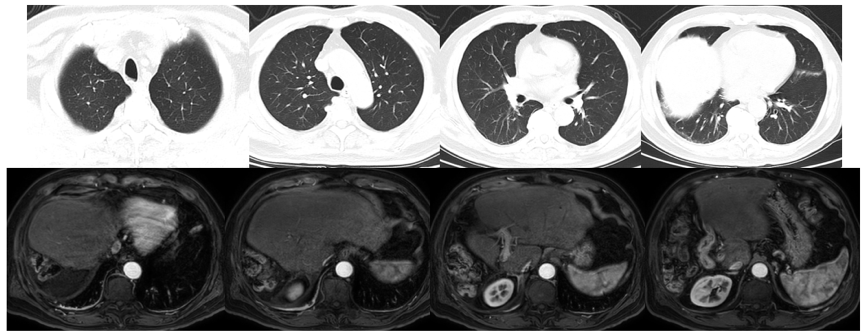

2020年4月20日上腹部MR示,原发性肝癌伴肝内及肝静脉浸润(图1)。中国肝癌(CNLC)分期Ⅲa期。

图1.2020年4月20日上腹部MR

2021年3月3日(根治术后4个月,瑞戈非尼 卡瑞利珠单抗持续治疗)复查CT示,肺部病灶消失,未发现新生病灶;复查MR示,肝脏残留病灶切除后未见明确新发病灶(图6)。AFP正常,疗效评价达到完全缓解(CR)。

图6.2021年3月3日复查CT及MR

2021年11月4日(根治术后1年,瑞戈非尼 卡瑞利珠单抗持续治疗)复查CT及MR示,肺部无明显病灶,肝脏无明确新发病灶(图7)。AFP正常。至今,持续缓解超20个月。

图7.2021年11月4日复查CT及MR